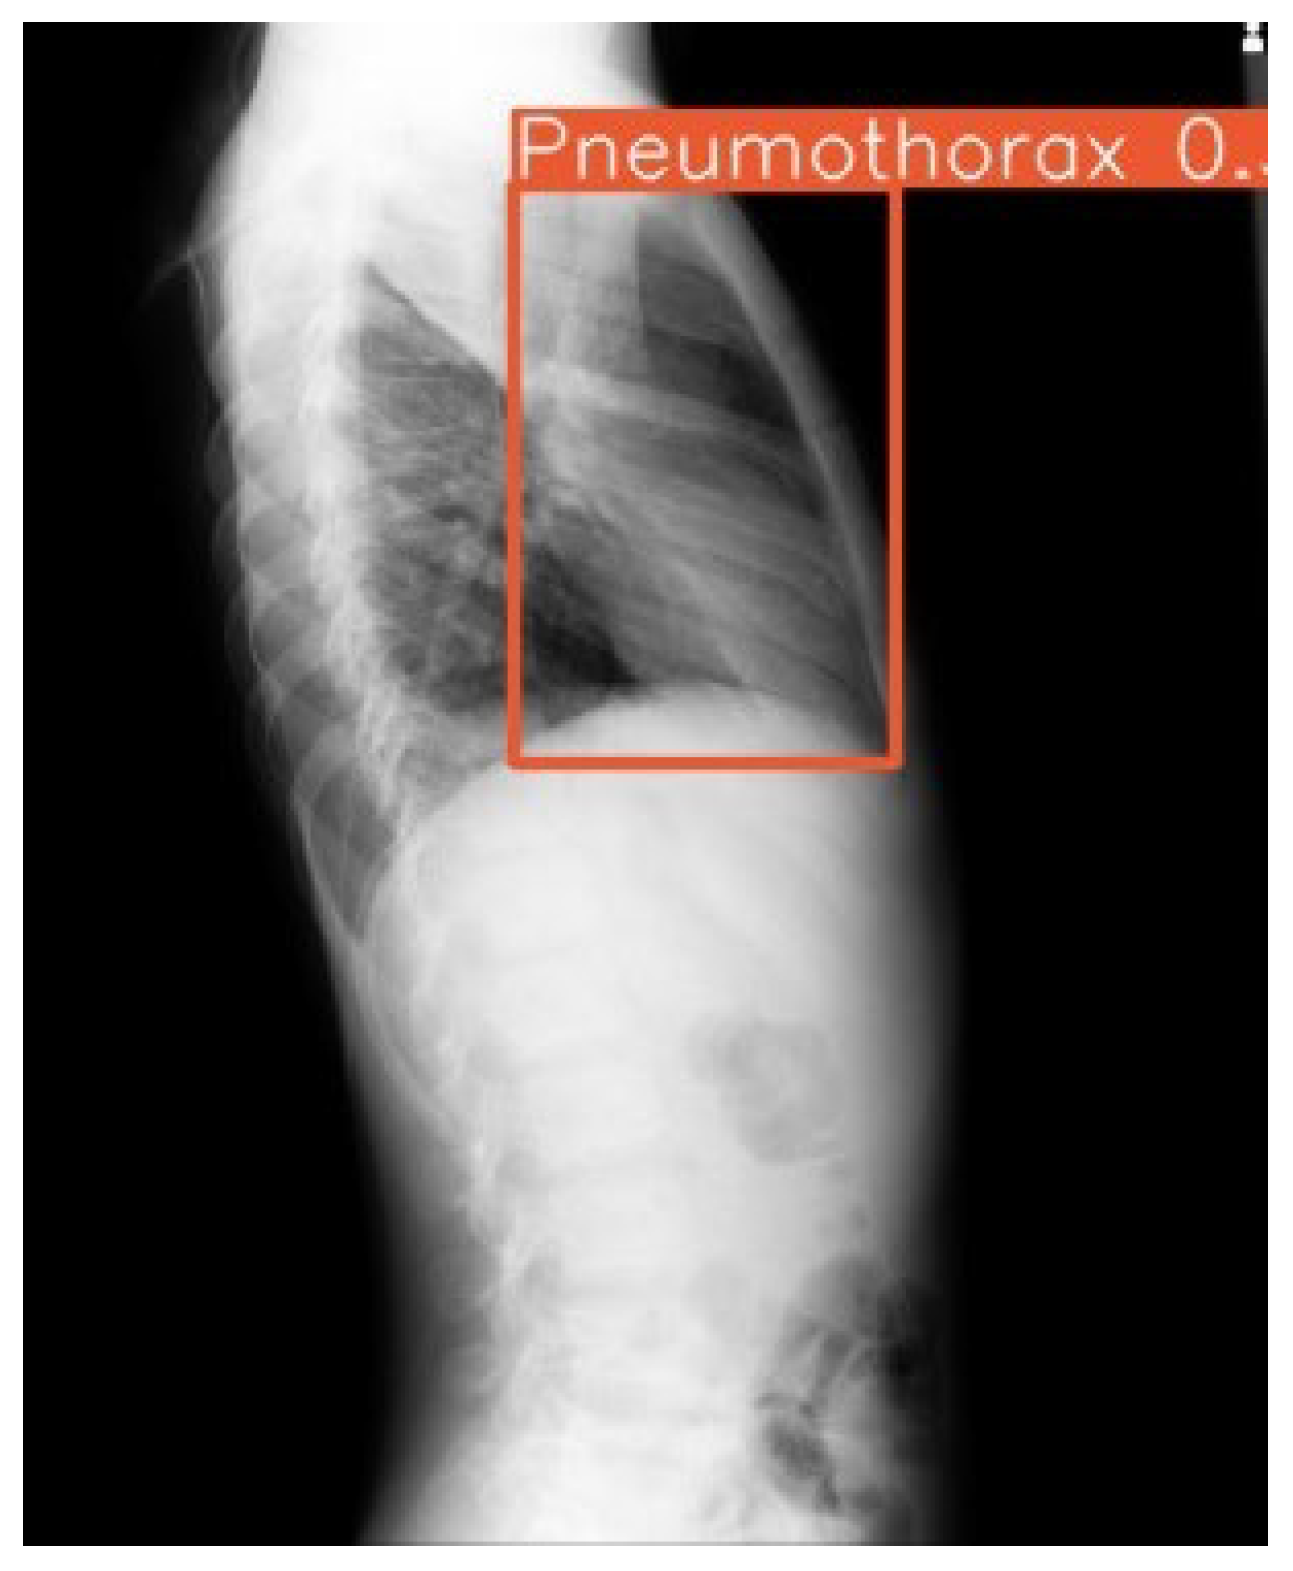

The system achieved an overall area under the receiver operating characteristic curve (AUC) of 0.86, indicating strong discriminatory ability. Model sensitivity reached 68%, while specificity was maintained at 99%. The mean average precision (mAP) of 0.93 confirmed adequate localization capabilities for the bounding box predictions across all pathology classes (Figure 3 and Figure 4).

The uniquely color-coded detection system for 14 pathologies minimized radiologist confusion by eliminating same-color bounding box overlap, while confidence scores enabled prioritization of high-certainty findings. Integration of both lateral and frontal views further streamlined chest X-ray interpretation workflow (Figure 5).

The model demonstrated potential for consistent performance across challenging imaging conditions, including poor-quality ICU anteroposterior films and lateral views with artifacts. This suggests acceptable resilience of the system to technical variations that could support deployment in diverse environments where ideal imaging conditions are not always achievable.

Figure 5. Example outputs with 14-color bounding boxes on multi-pathology cases in Row 1 (Frontal view) and Row 2 (Lateral view).